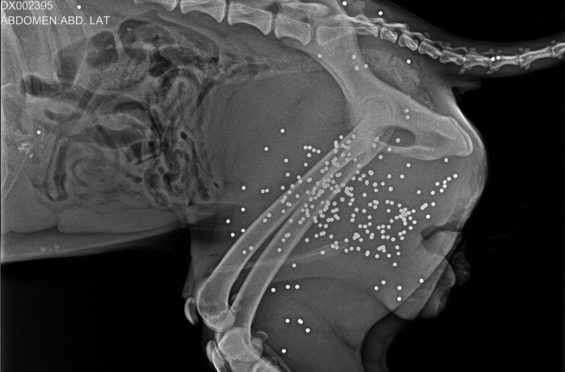

Рентген выжившей собаки из поселка Любимовка, на котором видно дробь Фото: Ольга Ефремова